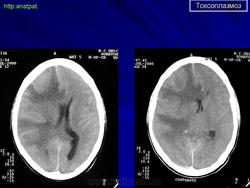

Пато морфологи я. Патоморфологические изменения при приобретенном токсоплазмозе изучены в экспериментах на животных. Установлено, что в центральной нервной системе развиваются явления некротического перивентрикулита, мелкие очаги некроза в субкортикальном белом веществе. В сосудах головного мозга, мягкой мозговой оболочки и хориоидальных сплетениях отмечаются признаки серозно-пролиферативного воспаления. Обнаруживаются также глазные патологоанатомические изменения (типа ретинита, хориоидита, иридоциклита) и изменения во внутренних органах (сердце, легкие, печень, селезенка).

Врожденный токсоплазмоз чаще, чем приобретенный, приводит к летальному исходу. В головном мозге умерших обнаруживаются более или менее значительные очаги обызвествления, участки размягчения мозгового вещества, полости, заполненные жидкостью. Как правило, отмечается гидроцефалия, обусловленная воспалительной и рубцовой облитерацией водопровода среднего мозга, отверстий Люшка или других участков ликворных путей. Истон-чение вещества полушарий мозга может достигать степени их полного исчезновения.

Особенно характерна триада симптомов: хореоретинит, гидроцефалия, очаги обызвествления в головном мозге. Кроме того, отмечаются менингеальные знаки, тонические и клонические судороги, парезы, параличи, олигофрения.

Неврологические симптомы могут сочетаться с пневмонией, миокардитом, гепатоспленомегалией, с выраженной желтухой. В спинномозговой жидкости отмечается лимфоцитарный плеоцитоз (до 500 • 106 в 1 л), ксантохромия (“канареечный” ликвор). На рентгенограмме черепа обнаруживаются обызвествления в глубинных отделах головного мозга, сосудистых сплетениях. Как и приобретенный, врожденный токсоплазмоз может протекать остро, подостро и хронически.